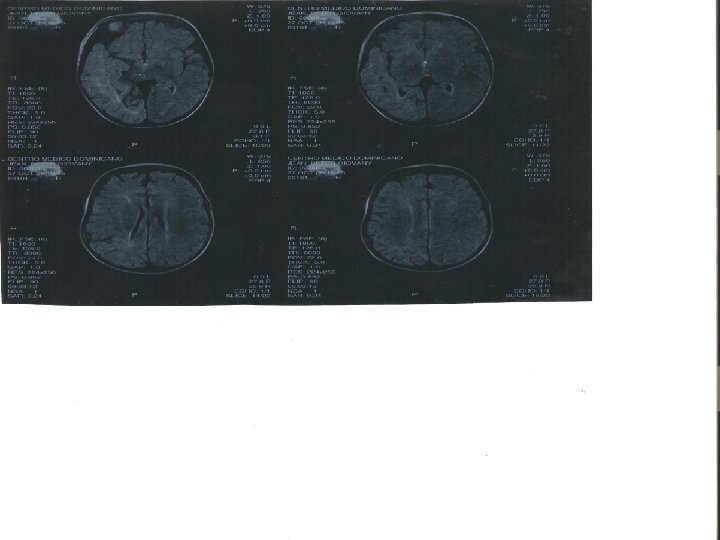

Case history • 5 years old, new onset seizures • No family history • New onset focal seizures with left hemiparesis with gait difficulties • Seen in DR, no dx, MRI normal, started on phenobarbital.

LINEAR NEVUS • Started on CBZ • Seizures controlled for past 6 months • No improvement on cognition or gait